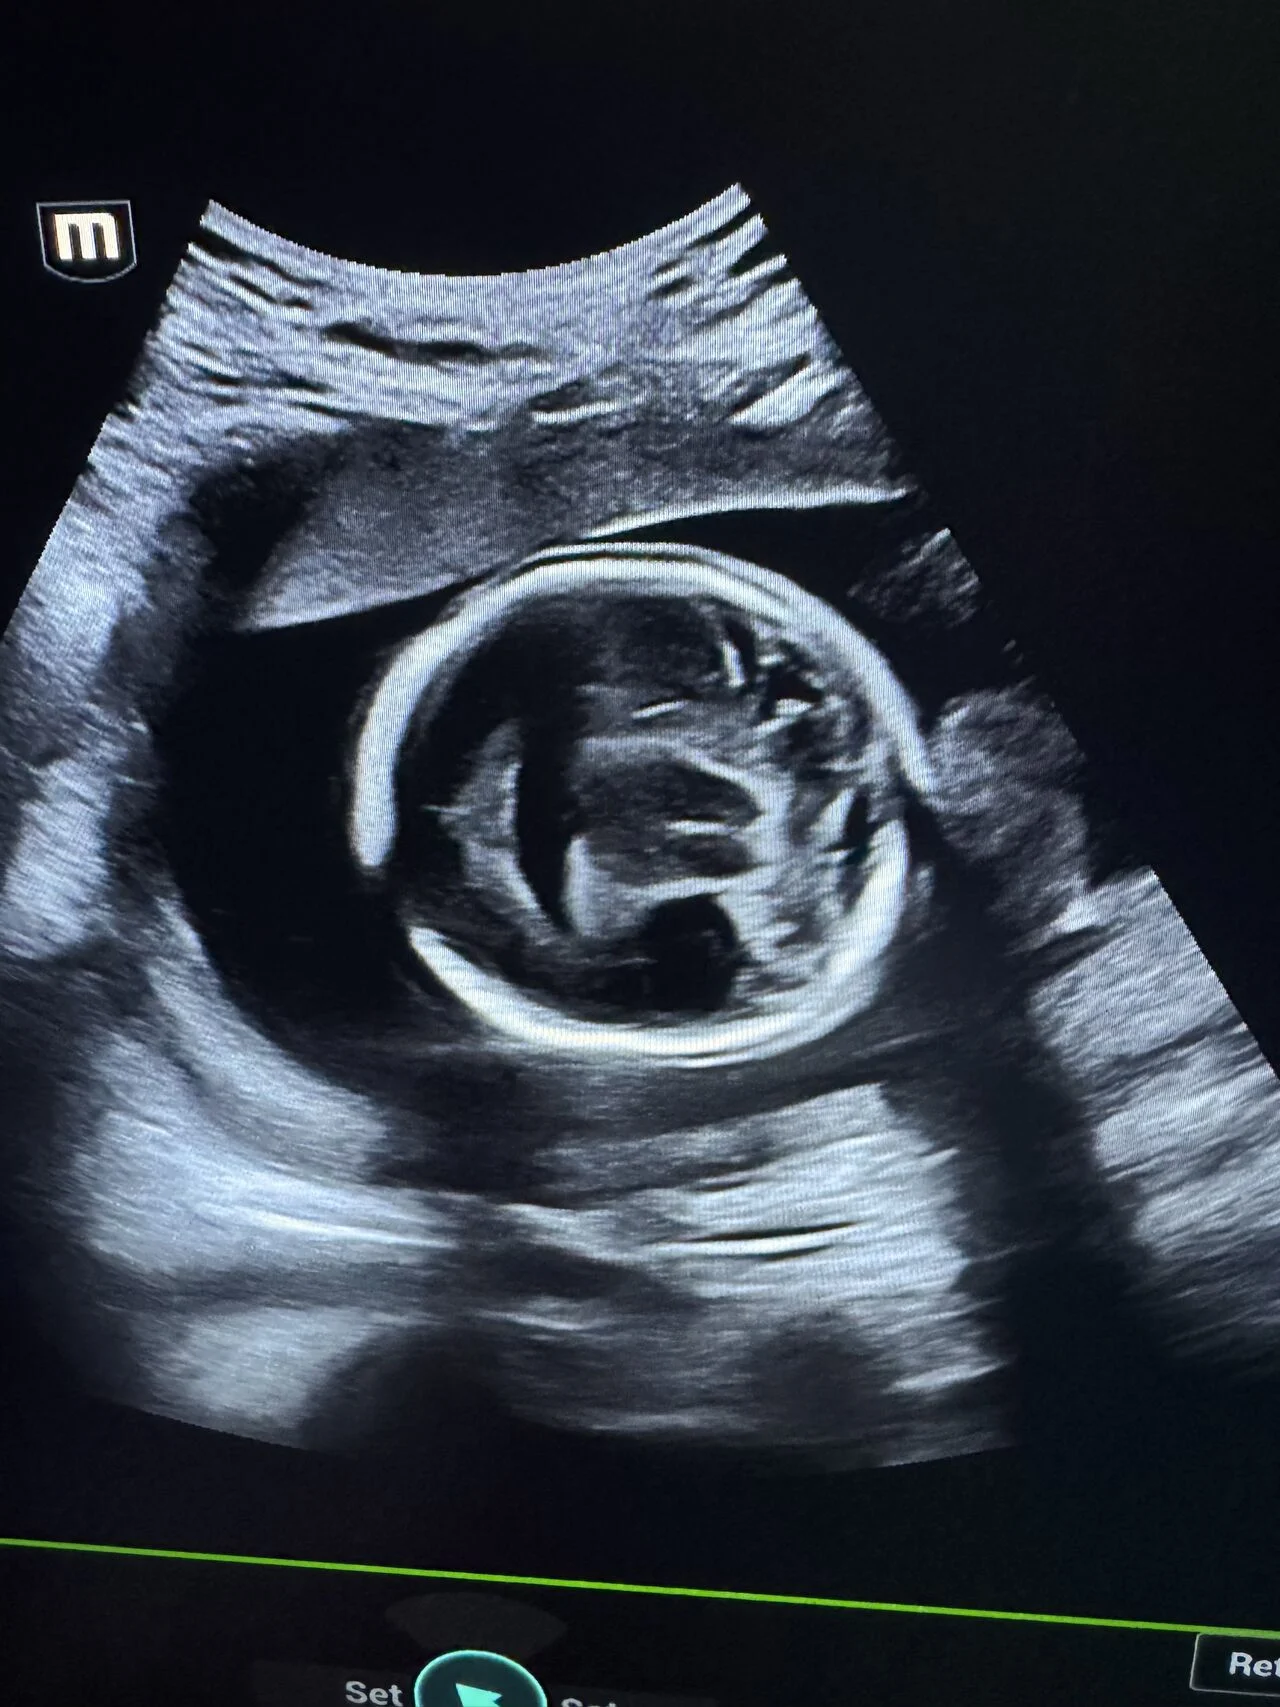

“Fetal Anomaly Case | Semilobar Holoprosencephaly

A prenatal ultrasound case demonstrating features of semilobar holoprosencephaly.

Key neurosonographic findings:

- Single midline ventricular cavity

- Fused thalami

- Partial absence of interhemispheric fissure

- Absent cavum septum pellucidum